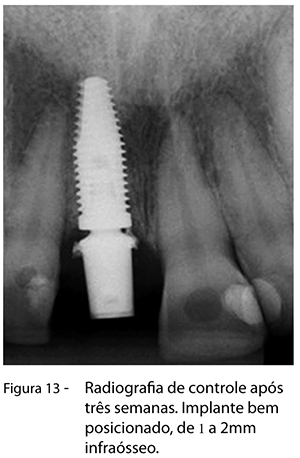

Foi utilizado o enxerto ósseo bovino composto GenMix (Fig. 7, 8) na parede óssea vestibular e, depois, procedeu-se à inserção do implante Alvim CM de 4,3 x 13mm com torque de 60N (Fig. 9, 10), e munhão de 4,5 x 6 x 1,5mm, com torque de 20N (Fig. 11), sutura e, por fim, instalação da coroa provisória (Fig. 12). Após uma semana, foi realizado um controle do local, e, após três semanas, a paciente retornou para novo controle da área, quando foi realizado um exame radiográfico, foram obtidas fotografias e fez-se o planejamento da cerâmica (Fig. 13, 14).